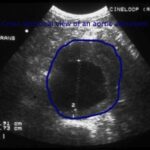

Health Right Here: What to expect with an abdominal aortic aneurysm ultrasound screening

Devin Zarkowsky MD FACSSpecial to Valley NewsAbdominal aortic aneurysm (AAA) is a serious condition that occurs when the large blood vessel bringing blood from...